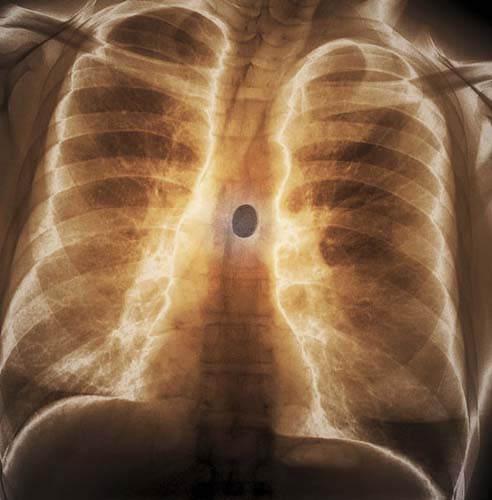

60 yaşında bir şizofreni hastası, bronşlarındaki yabancı bir cisim.